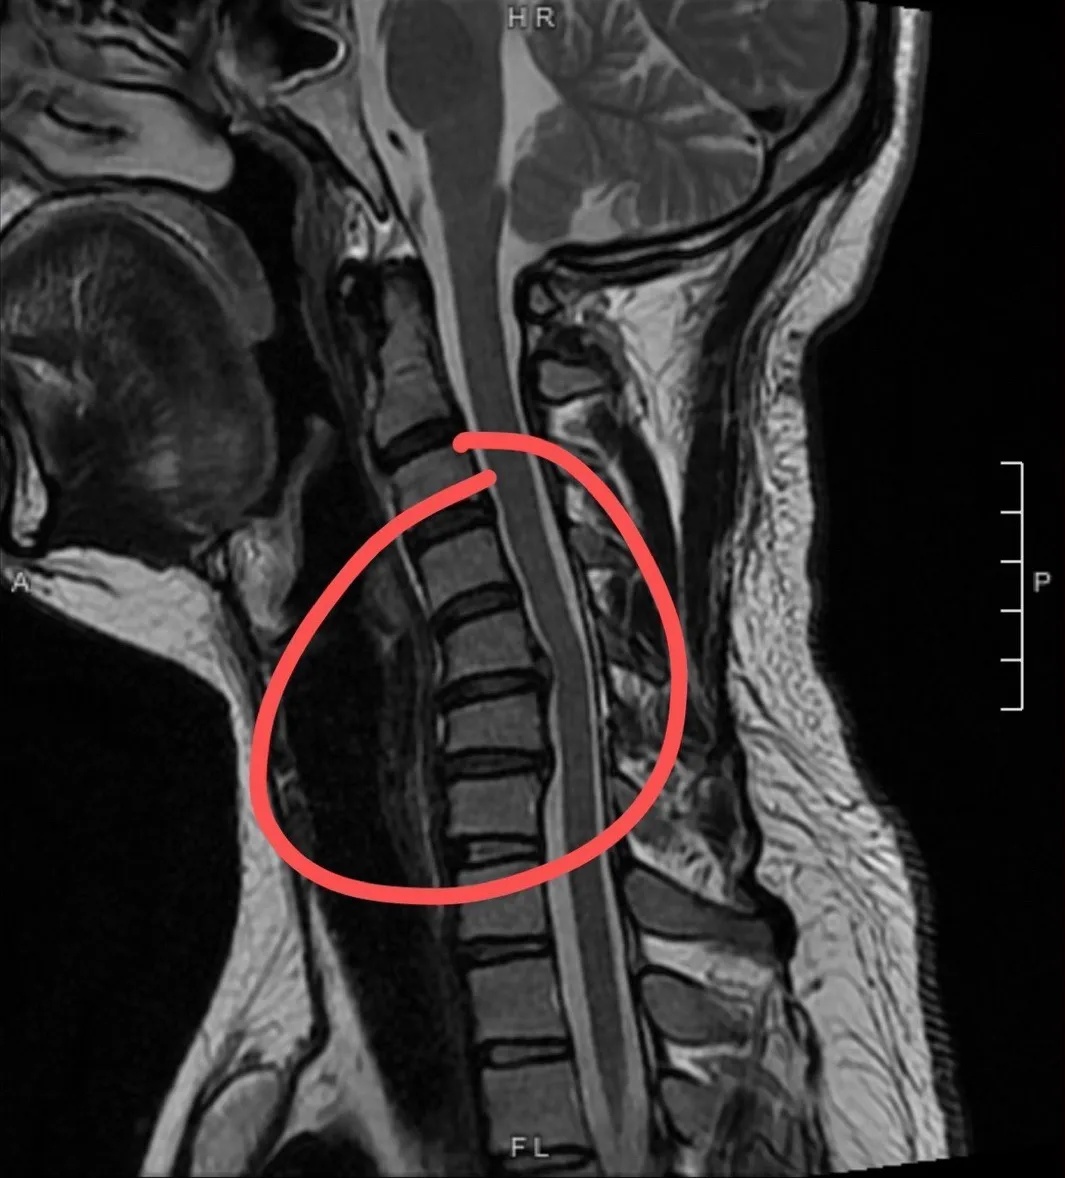

劝你们放下手机,多看天空。颈椎反弓,这下好了……

颈椎反弓

楼主说,他查出来颈椎反弓,颈椎中间那段向后突出,压迫到神经和动脉了。

目前来说,做牵引可能会有缓解,如果再严重的话,就只能手术治疗了。

正常颈椎曲度生理性前凸,它既保证了颈椎活动的高度灵活性,又减轻了颈椎间盘的重力负荷,使颈椎处于最佳的力线状态下工作。

如果没有生理弯曲,颈椎会出现僵直,甚至向相反的方向弯曲,就称为颈椎反弓。

颈椎反弓会引起很多疾病。

首先是颈椎动脉受压,会引起大脑供血不足,而与颈椎相关的骨关节组织因挤压,提早产生增生、骨刺、韧带肥厚、椎间盘突出而压迫颈部脊髓、神经根、椎动脉等,产生一系列生理病理变化,出现颈椎病相关的临床症状,如颈项部痛、肩臂痛、肢体麻木、恶心呕吐、头晕头痛、失眠、健忘等,严重的还会引起瘫痪。